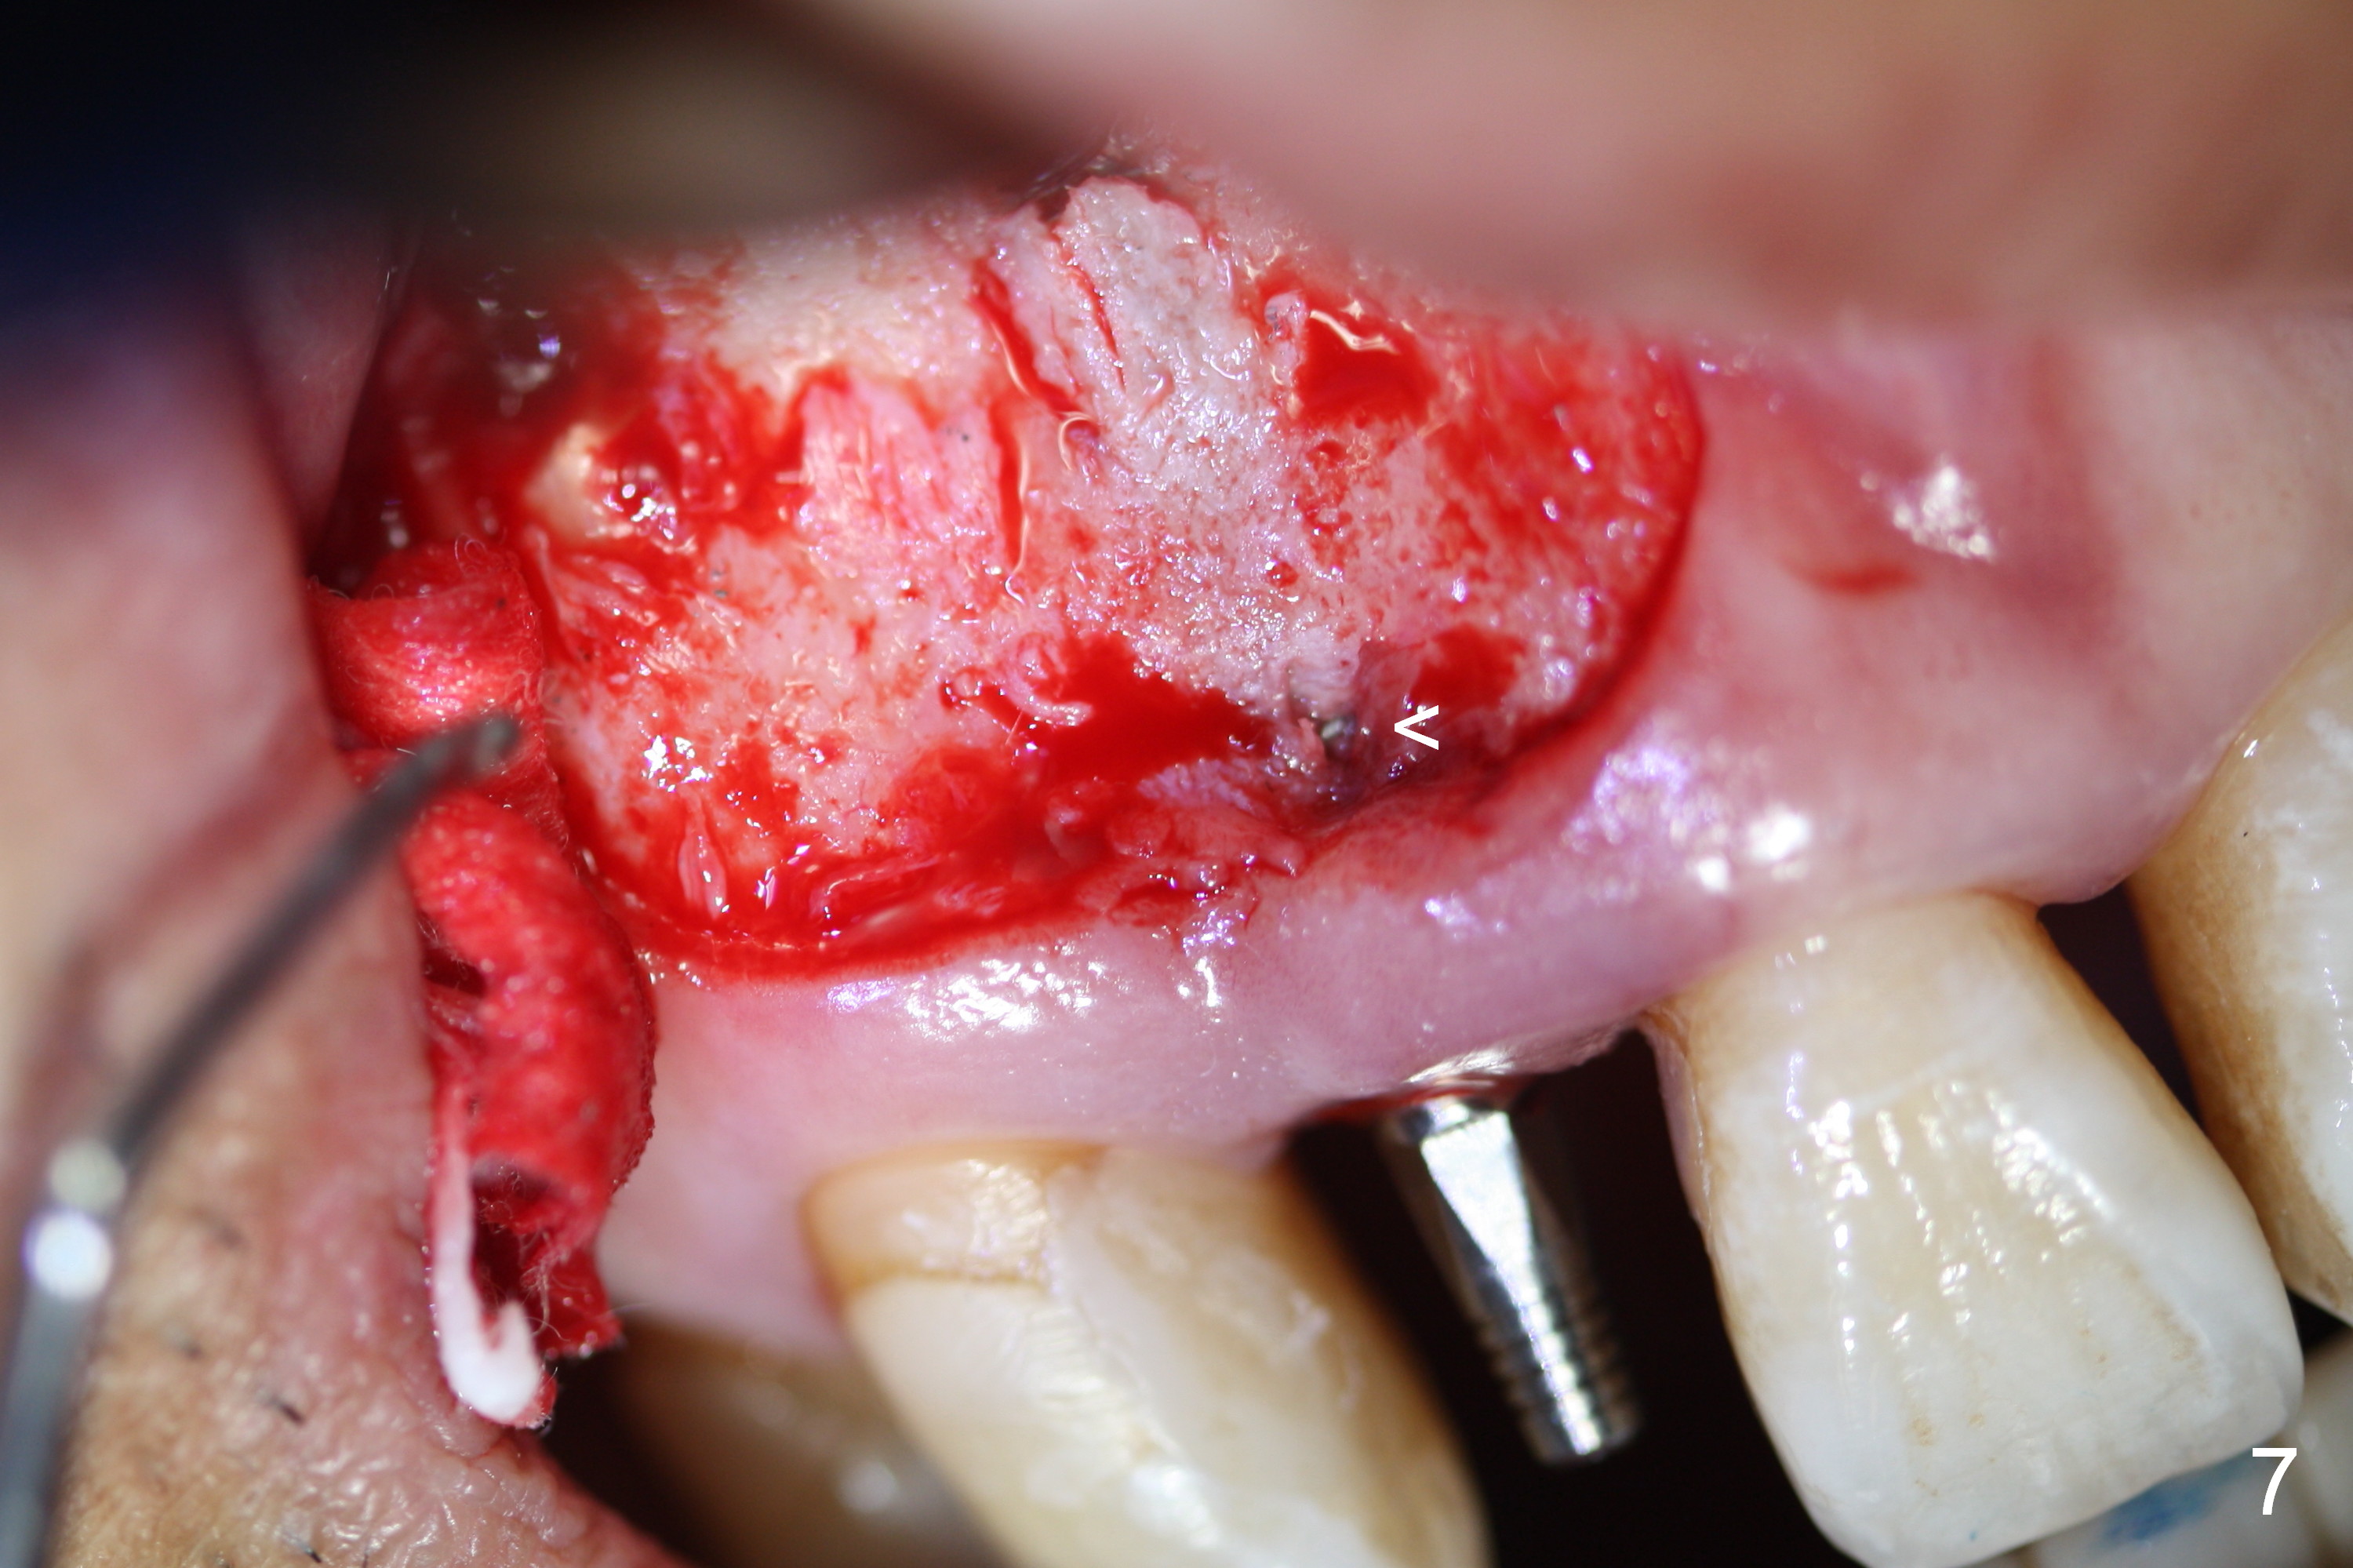

Preop exam shows the apparent wide ridge at #7 (Fig.1). What is ignored preop is the concavity in the apical buccal region (Fig.2 *). When a 3x16(4) mm 1-piece implant is being placed (Fig.3 *, flapless), the apical buccal plate vibration is felt. The biggest mistake is that initial osteotomy is ~ 6 mm shy of the implant length, partially because of 6 mm gingival height. Since the tooth #6 is symptomatic after RCT with paste overfill (Fig.4 >), apicoectomy is contemplated at #6 with exploration of the buccal plate at #7 (Fig.5). Since the implant appears to be long enough, implant apical resection is performed (Fig.6). Since there is coronal thread exposure due to previous periodontitis (Fig.7 <), bone graft is placed in these 3 defective areas after decortication.

Extending the initial osteotomy to the full length of the implant is critical. If perforation is detected early, the trajectory can be changed. Incision should be made if there is no CBCT study. The incision heals 1 and 4 weeks postop (Fig.8,9). The patient returns for final restoration 6 months postop. Apical defects appear to have healed at #6 and 7 (Fig.10,11). Fig.12 is taken 11 months postop and 5 months post cementation. The patient has an accident 9 months post cementation. In fact the implant is alright, while the tooth #6 fractures and #8 subluxates.